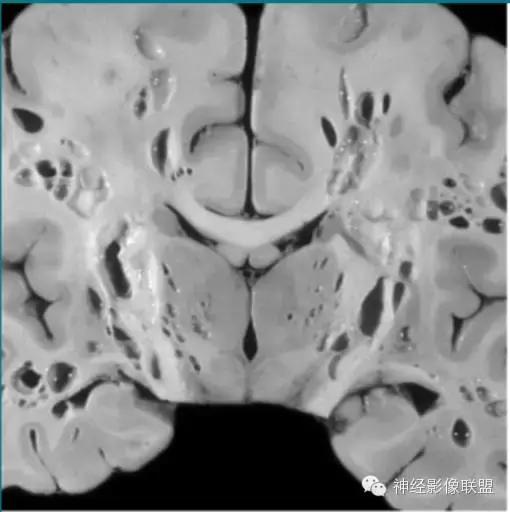

VR间隙扩大